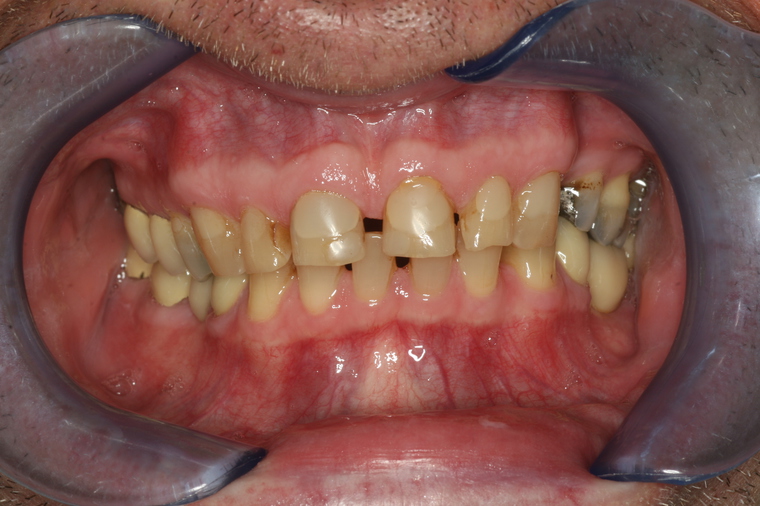

Viele Kunden die zu uns nach Salzburg kommen benötigen eine Generalsanierung der Zähne. Gründe dafür sind Zahnarztangst, Zeitmangel und schlechte Erfahrungen in der Kindheit. Unser Konzept ist genau auf diese umfangreichen Fälle abgestimmt:

Bei einer Generalsanierung müssen alle zahnmedizinischen Bereich in Betracht gezogen werden, dies beginnt bei der Aufklärung und Prophylaxe, gefolgt von Zahnfleischbehandlungen und Kariestherapie, eventuellen Zahnentfernungen, Knochenaufbauten und wird durch ästhetischen Zahnersatz abgeschlossen. Unser Recall-System hält die erreichte Zahnsanierung über lange Jahre stabil.